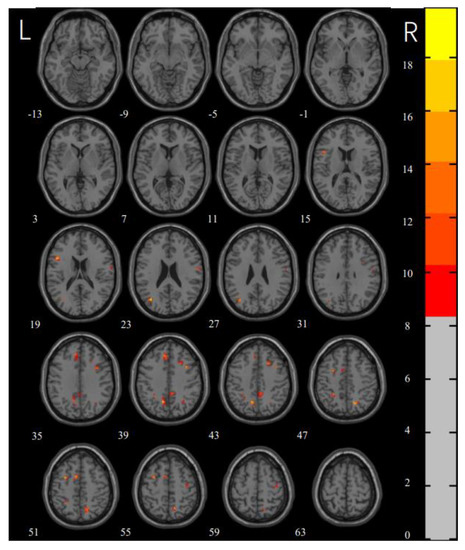

| MNI x, y, z | Voxels | F | Side | Brain Region | |

|---|---|---|---|---|---|

| CL1 | −48, 15, 18 | 12 | 17.3371 | L | inferior frontal gyrus |

| CL2 | −36, −69, 24 | 14 | 19.83114 | L | middle occipital gyrus |

| CL3 | 60, −6, 21 | 11 | 10.8797 | R | postcentral gyrus |

| CL4 | 36, 12, 39 | 10 | 14.4576 | R | middle frontal gyrus |

| CL5 | 18, −63, 48 | 17 | 16.4027 | R | precuneus |

| CL6 | −9, 36, 39 | 22 | 12.6563 | L | medial superior frontal gyrus |

| CL7 | −12, −60, 39 | 24 | 18.7764 | L | precuneus |

| CL8 | 21, 18, 42 | 11 | 13.9385 | R | superior frontal gyrus |

| CL9 | −27, −45, 48 | 12 | 13.076 | L | inferior parietal gyrus |

| CL10 | −30, 3, 51 | 11 | 16.1396 | L | middle frontal gyrus |

| CL11 | −9, 6, 51 | 13 | 14.7148 | L | supplementary motor area |

| CL12 | 39, −12, 57 | 11 | 11.5019 | R | precentral gyrus |

| Washers > HCs | |||||

| CL1 | −45, 15, 18 | 14 | 5.8462 | L | inferior frontal gyrus |

| CL2 | 51, −30, 33 | 10 | 4.1435 | R | supramarginal gyrus |

| CL3 | −27, −51, 39 | 10 | 4.6492 | L | inferior parietal gyrus |

| CL4 | −12, −60, 39 | 39 | 5.1497 | L | precuneus |

| CL5 | 6, −45, 42 | 25 | 4.1893 | R | precuneus |

| CL6 | 18, −63, 48 | 23 | 5.6277 | R | precuneus |

| CL7 | −30, 3, 51 | 19 | 5.3576 | L | middle frontal gyrus |